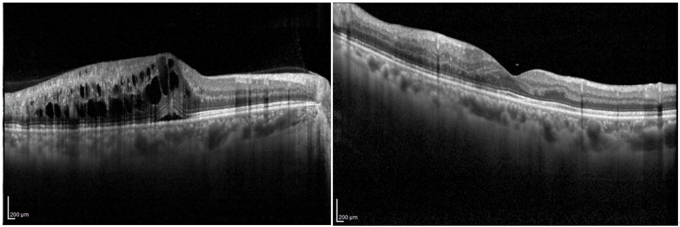

또한 망막정맥폐쇄는 반대쪽 눈에서 발생하거나 양안에 순차적 또는 동시 발병할 가능성이 망막동맥폐쇄에 비해 상대적으로 높은 편으로, 초기 진단 이후에도 장기적인 경과 관찰과 체계적인 관리가 필요하다. 이 경우 조기 진단을 바탕으로 항혈관내피성장인자(anti-VEGF) 주사 치료 등 적극적인 치료 전략을 통해 합병증 발생을 최소화하는 것이 중요하다.

망막혈관폐쇄가 이미 발병했다면 혈압 및 혈당을 관리하더라도 발병 이전의 상태로 완전한 회복을 기대하기는 어렵다. 다만, 전신 상태를 안정적으로 관리하면서 치료를 병행할 경우 망막 출혈 흡수와 황반부종 감소를 통해 시력 저하를 억제하고 증상 개선을 기대할 수 있다.